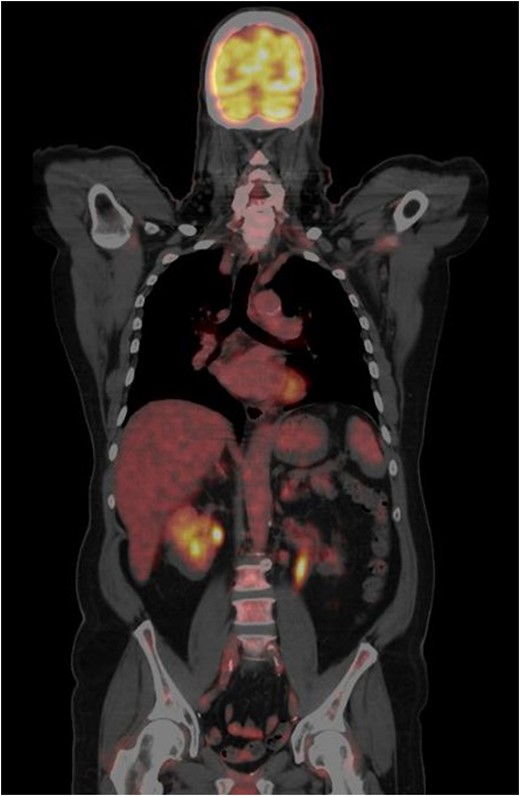

CT-PET performed after surgery showing metastatic disease with local recurrence of the mass extending into the cystectomy bed.